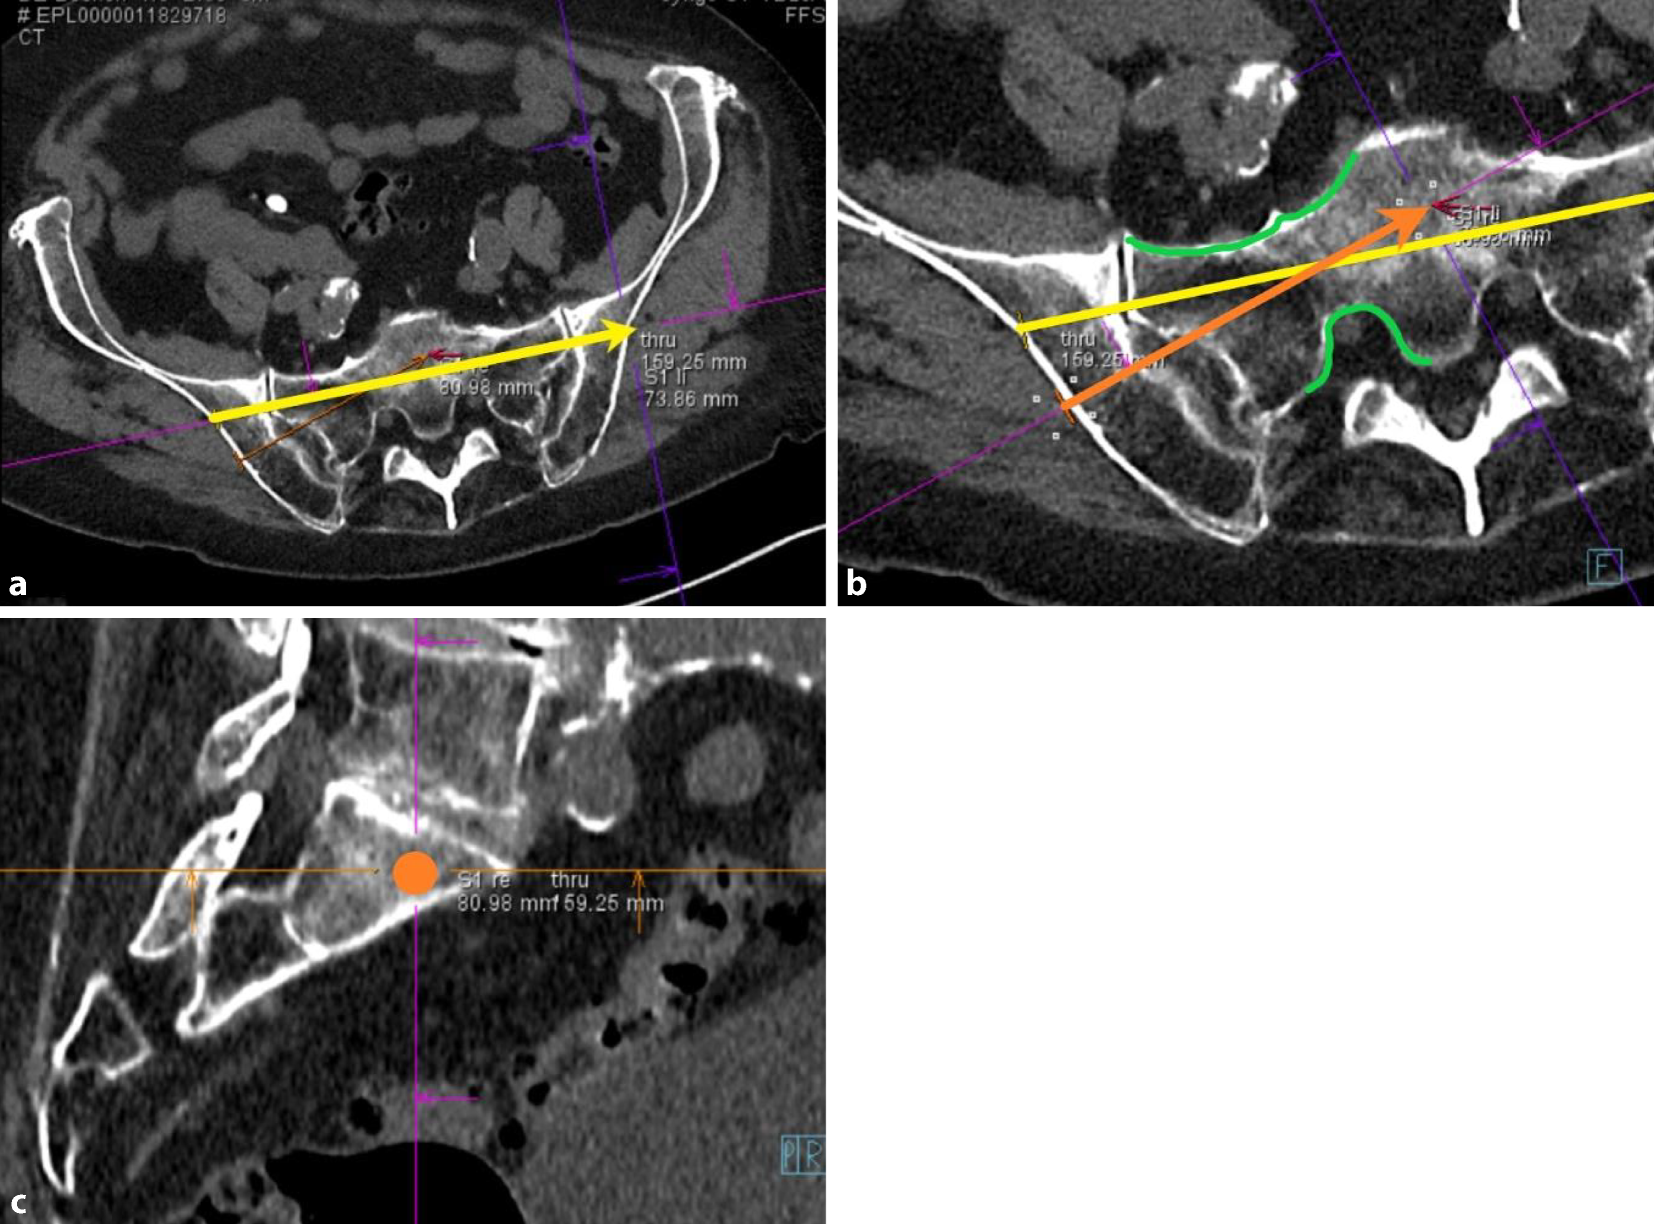

• Employ the diagnostic CT to measure the angles for the personalized inlet and outlet view, which are critical aspects of the presented method (Fig. 1). A comprehensive explanation of the personalized inlet and outlet angles is illustrated in appendix 2

Fig. 1

Determination of the personalized inlet angle (α) and personalized outlet angle (β) in the sagittal view. The dashed line encircles the bony part of the symphysis, the solid line encircles the sacral vertebral bodies, the black arrow points to the S1 body

To facilitate an efficient workflow, screw pathway planning on the diagnostic CT is performed while preparing the patient in the hybrid theatre. The process of planning the screw pathways involves several steps. Firstly, ensure symmetrical alignment of the pelvis in all three planes. Then, an auxiliary pathway is defined (yellow arrow, a), to achieve the lateral view intraoperatively (Fig. 5) which is essential to determine the optimal entry point for the SI screw. The predefined personalized inlet, outlet, and lateral views (see appendix 2) are saved by the software system to allow swift intraoperative transition between these views. The next step involves planning the desired screws in the coronal and axial slices (orange arrow and dot,  bc). Two critical factors to consider are: ensuring the entry point is not too dorsal to avoid conflict with the operating table due to supine positioning of the patient, and the planned screw ideally transversing the corridor in the S1 body centrally between the ventral sacral cortex and the neuroforamen (green lines, b) [5]. The correct intraosseous path can be checked by scrolling forward and backward along the planned screws in the sagittal plane. These planned screw pathways can be projected with dotted lines on all fluoroscopic views intraoperatively (as shown in Figs. 67, and 9)